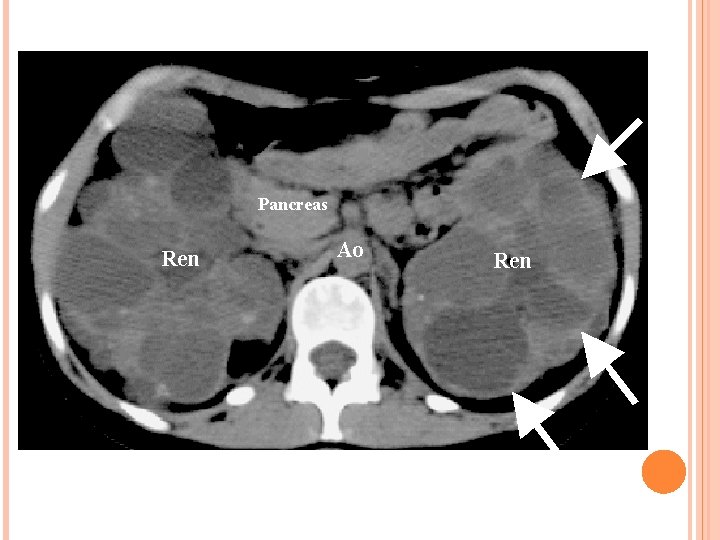

Rein : kystes rénaux – Apparaissent vers 20 ans – Douleurs lombaires et abdominales – hématurie macroscopique et hémorragie intra kystique – Infection urinaire et infection kystique – lithiases urinaires – HTA – IRCT – Cancer du rein

Rupture des vaisseaux de la paroi du kyste vers l’intérieur Douleurs sans hématurie TDM kysteavec haute densité spontanée

Diagnostic : – Arbre généalogique – Écho rénale : Inférieur a 30 ans Au moins 2 kystes uni ou bilatéraux 30 – 59 ans Au moins 2 kystes dans chaque rein Supérieur à 60 ans Au moins 4 kystes dans chaque rein – Dépistage des autres atteintes que le rein (écho hépatique, écho cardiaque, coloscopie, angio IRM cérébrale) – Dépistage des cas familiaux